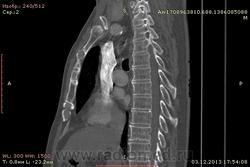

Доброго времени суток уважаемые форумчани! :)Провели исследование КТ грудной клетки с контрастированием, для выявления аневризмы грудного отдела аорты. В результате увидели это:

Говорил с врачом, у больного был плеврит неизвестной давности.

??? Аневризму честно не вижу (мало опыта в определении аневризм). Тромбоз в бассейне верхней полой вены. В левом легком обызвествленные плевральные шварты? как исход осумкованного плеврита неизвестной давности?

на VRT-реконструкции. плотность до + 1000 HU. видел такое как посттуберкулезные обызвествления плевры, надо завтра ещё раз поговорить с лечащим врачом, может ошиблись

намерил аорту, всё таки есть аневризматическое расширение луковицы